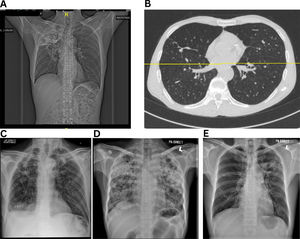

Most studies on PTLD risk are cross-sectional or retrospective, limiting causal inference or identifying early predictors [7]. The absence of simple, scalable diagnostic tools for resource-limited settings further compounds the challenge. Although some studies followed up beyond 6–9 months post-treatment, most focused primarily on spirometry, offering limited insights into PTLD's natural history, and progression [39,40,45]. Imaging remains central to diagnosis: chest radiographs may reveal residual fibrotic bands with volume loss, bronchiectasis, pleural thickening, cavities, or calcifications [46] (Fig. 2), while high-resolution computed tomography (HRCT) provides more detailed characterization [36]. Nevertheless, radiologic severity often poorly correlates with symptoms or functional decline, complicating clinical interpretation [47].

Representative radiographic and high-resolution CT images of patients with microbiologically confirmed pulmonary TB. (A) Extensive right upper lobe volume loss, fibrotic scarring, and tracheal deviation to the right—hallmarks of post-tuberculosis fibrotic lung damage, (B) Bilateral bronchiectasis with dilated bronchi, parenchymal scarring, (C) Cavitary lesions and right upper lobe fibrosis, (D) and (E) Severe fibrosis and bronchiectasis.